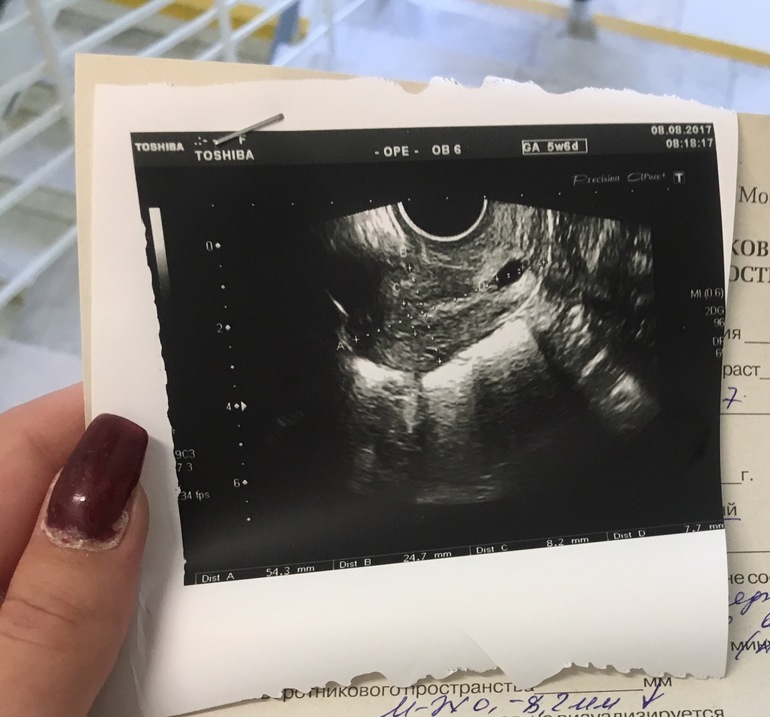

Для выполнения УЗИ на раннем сроке должны быть показания. Основная цель —установить маточную локализацию плодного яйца: маточная, внематочная; вторая цель — определить жизнеспособность плодного яйца. Анатомия и все остальное — уже ближе к первому скринингу в 11-14 недель, но УЗИ в ранние сроки в основном преследуют эти две цели. По определенным ультразвуковым параметрам их возможно сделать.